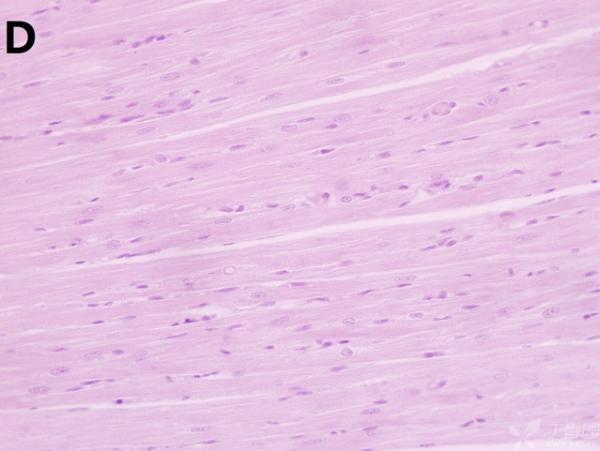

ÎÒ½«Ã¿¸ö×éÖ¯ÅÄÁË3¸öÊÓÒ°£¬ÒÔ±ã×ۺϷÖÎö£¬Âé·³¸÷λ°ïÎÒ°ÑA¡¢B¡¢C¡¢D¡¢E¡¢F¡¢GµÄËðÉË´óСÅŸö˳Ðò ÔÙ°ÑA¡¢B¡¢C¡¢H¡¢I¡¢JËðÉ˵ÄÑÏÖØ³Ì¶ÈÅŸöÐò¡£¸ÃÎÊÌâÒ²ÔÚ¶¡ÏãÔ°ÉÏÇóÖúÁË£¬Á´½Óhttp://www.dxy.cn/bbs/topic/23986562 A1.jpg A2.jpg A3.jpg B1.jpg B2.jpg B3.jpg C1.jpg C2.jpg C3.jpg D1.jpg D2.jpg D3.jpg E.jpg F1.jpg F2.jpg F3.jpg G1.jpg G2.jpg G3.jpg H1.jpg H2.jpg I.jpg I2.jpg I3.jpg J.jpg J2.jpg J3.jpg [ Last edited by ÀëÈËÏæÑÅÀá on 2012-10-9 at 21:11 ] |